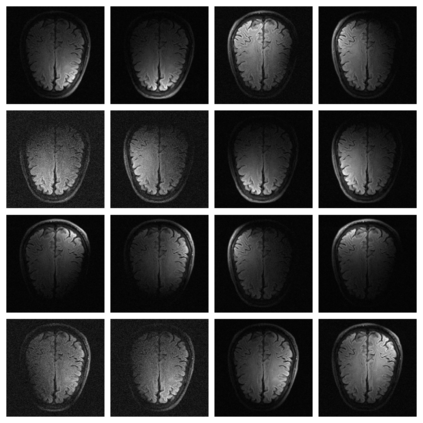

In spite of its extensive adaptation in almost every medical diagnostic and examinatorial application, Magnetic Resonance Imaging (MRI) is still a slow imaging modality which limits its use for dynamic imaging. In recent years, Parallel Imaging (PI) and Compressed Sensing (CS) have been utilised to accelerate the MRI acquisition. In clinical settings, subsampling the k-space measurements during scanning time using Cartesian trajectories, such as rectilinear sampling, is currently the most conventional CS approach applied which, however, is prone to producing aliased reconstructions. With the advent of the involvement of Deep Learning (DL) in accelerating the MRI, reconstructing faithful images from subsampled data became increasingly promising. Retrospectively applying a subsampling mask onto the k-space data is a way of simulating the accelerated acquisition of k-space data in real clinical setting. In this paper we compare and provide a review for the effect of applying either rectilinear or radial retrospective subsampling on the quality of the reconstructions outputted by trained deep neural networks. With the same choice of hyper-parameters, we train and evaluate two distinct Recurrent Inference Machines (RIMs), one for each type of subsampling. The qualitative and quantitative results of our experiments indicate that the model trained on data with radial subsampling attains higher performance and learns to estimate reconstructions with higher fidelity paving the way for other DL approaches to involve radial subsampling.